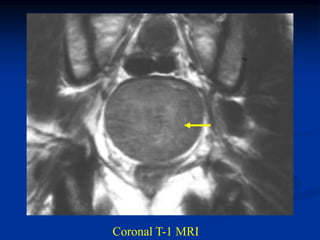

Case #1097

14 year male with

adamantinoma distal

tibia and fibula

Coronal T-1 MRI